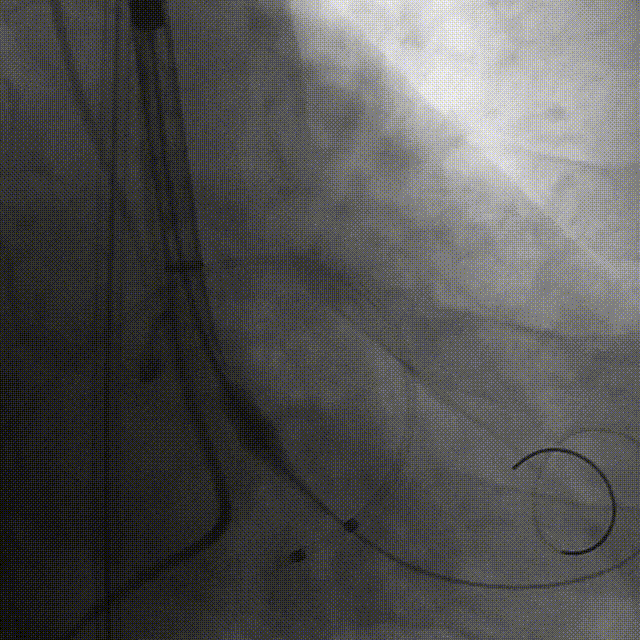

谷兴华教授 山东大学齐鲁医院 锚定终身获益,重视首次干预选择:心脏瓣膜病介入中心成立2年多来,中心核心目标始终保证在解决即刻病症的基础上,护航患者的全生命周期健康管理。 摆在眼前的实际是日益年轻化的患者群体,这意味着我们从手术伊始,就必须将患者未来数十年的生活质量和再次干预风险纳入核心考量,主动规划长远的健康路径。此次患者选择更具耐久的新型干瓣技术,力求减少患者未来再次干预的风险。同时,通过“TAVR+PCI一站式手术”这样的团队协作模式,系统性地处理多重心血管问题,避免分次手术的负担与风险,这正是我们中心一直秉持的“心脏瓣膜病全生命周期管理”理念的实践。让我们一起探索从“治已病”真正迈向“管长远”,让更多的患者获益! 病例特点速览 本次救治的患者,病情呈现“基础病交织、多病变叠加、锚定风险高”三大核心特征。患者为65岁,女性,病变特点TypeI型二叶瓣、轻度钙化,锚定风险大;同时患有冠状动脉粥样硬化性心脏病、慢阻肺(COPD);既往有长期吸烟饮酒史、脑梗死病史、高血压病史、乙肝小三阳病史及腹股沟疝修补手术史,患者STS评分9.32%,外科手术高危,经齐鲁医院瓣膜中心团队评估认为:局麻下“一站式TAVR+PCI”为最优治疗方案,结合患者较年轻,可选择具有长期耐久性的干瓣。 患者病史 主诉:活动后胸闷、憋喘余,加重20余天 既往史:30年前确诊乙肝小三阳,否认其他传染病史;有右腹股沟疝修补手术史,高血压病史,近期规律服药控制。 现病史:患者1年前出现活动后胸闷、憋喘,休息可缓解,为进一步诊治。2月前因“突发意识模糊、口齿不清”于当地医院入院,诊断为“急性脑梗死”,予以微创介入取栓治疗,恢复可,未遗留后遗症。20天前于当地医院再次入院行脑血管支架植入术,术后出现胸闷、憋喘,伴大汗,行心脏超声提示主动脉瓣重度狭窄,并行冠脉造影检查,予以药物治疗。10天前就诊于我院复查心脏超声提示二叶式主动脉瓣,主动脉瓣狭窄(重度)并反流(轻度)。患者现仍感胸闷,双上臂疼痛不适,咳嗽咳痰,日常活动受限。为行进一步治疗就诊于我院,门诊以“主动脉瓣狭窄、冠状动脉粥样硬化性心脏病”收入院; 个人史:吸烟50年,饮酒50年; 体格检查:体温:36℃,脉搏:67次/分,呼吸:18次/分,血压:143/76mmHg; 术前超声提示: 二叶式主动脉瓣主动脉瓣狭窄(重度)并反流(轻度);升主动脉扩张、左心扩大三尖瓣反流(少量);左室充盈异常;CW测最大压差86mmHg,平均压差43mmHg,最大血流速度463cm/s,连续方程法估测主动脉瓣口面积0.78cm² 术前CT评估 Type1型二叶瓣,轻度钙化、左右融合,主动脉瓣环径25.3mm,LVOT直径25.5mm,鱼嘴空间约26.6mm,主要靠瓣环锚定。窦部空间大、左右融合,VTC空间足够,无冠脉风险 ;左室内径正常,主动脉瓣环水平夹角49.6°。外周双侧入路内径可,髂外动脉存在散在钙化、双侧入路能够支持20F大鞘通过,右股低分叉,主动脉弓距弓角可。 个性化手术策略:局麻一站式方案+创新瓣膜精准适配 入路选择:主入路:右侧股动脉(右股分叉上方1cm处穿刺);辅入路:左侧股动脉;器械:20F大鞘; 手术流程规划:局麻下行同期一站式TAVR+PCI,植入ProStyle A®预装干瓣; 瓣膜选型与预处理:瓣膜型号:ProStyle A® AV32;不预扩; 定位与释放方案:初始定位:瓣上3mm处释放,瓣膜自然下滑至工作位,最终目标“0-瓣下5mm位”。 手术过程:局麻一站式操作+创新瓣膜植入,无缝衔接 手术团队按预设方案稳步推进,实现TAVR、PCI与ProStyle A®干瓣植入的无缝衔接: 1.术前准备:完成影像评估、血管通路建立,确认ProStyle A® AV32瓣膜状态; 2.PCI治疗:通过主入路完成左冠造影,前降支、对角支明显狭窄,精准植入两枚支架,恢复冠脉血供; 左冠造影,前降支、对角支病变 PCI后造影,病变血管充盈良好 3.主动脉根部造影:确认主动脉根部解剖结构,并精准跨瓣; 主动脉根部造影 精准跨瓣 4.干瓣植入:将瓣膜输送过弓、过瓣,并精准定位; 输送系统柔顺过弓 精准定位 5.术中评估:释放瓣膜至工作状态,再次造影评估,位置满意,完全释放瓣膜; 工作位评估 32号瓣膜稳定脱钩 6.释放后造影:可见瓣膜位置满意、形态良好,无明显瓣周漏。 最终造影,位置形态良好,无瓣周漏 术后超声探查:位置(瓣下4mm)、形态良好,无瓣周漏,PGmean=10mmHg。 此次手术的成功,体现了山东大学齐鲁医院心脏瓣膜病介入中心秉承的“心脏瓣膜病全生命周期管理”的理念和团队协作的临床能力。面对低龄高风险复杂病例,团队通过术前充分评估、术中精细操作,结合具有长期耐久性的干瓣技术,以一站式方案改善患者症状、提高生活质量并延长寿命,为类似病例的诊疗提供宝贵经验。 专家简介 谷兴华 山东大学齐鲁医院(点击查看专家详细简历)